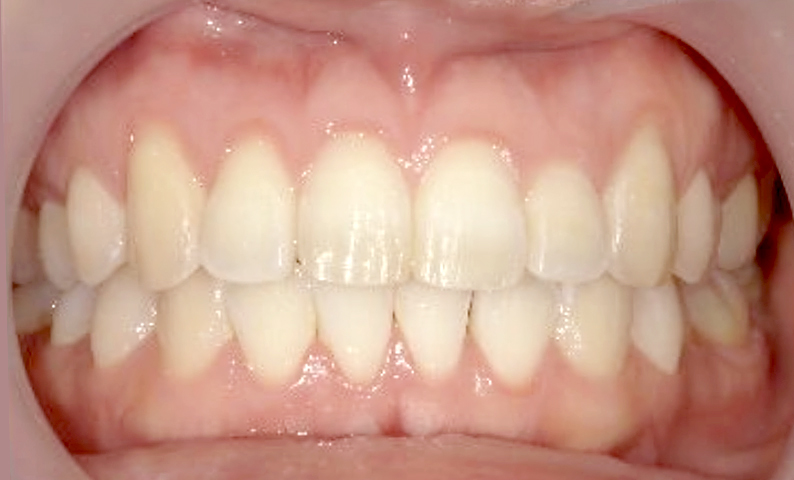

症例_025 上顎だけの部分矯正

治療期間:7ヶ月金額:30万円+税女性前歯のガタガタ上の前歯だけ